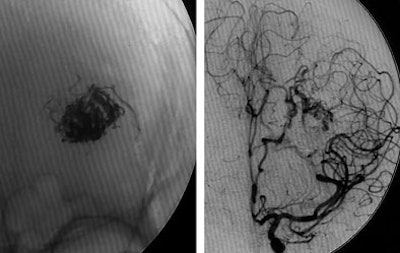

| Digital subtraction angiography shows arteriovenous malformation at presentation (top, below) and two weeks postembolization (bottom) with endovascular administration of ethylene vinyl alcohol copolymer embolization agent (Onyx, Micro Therapeutics, Irvine, CA). The patient had repetitive transient ischemia attacks due to cerebral steal from the AVM. Images courtesy of Dr. Michael Forsting. |

In another example, a patient with an AVM located in the speech center of the patient's brain was a "No-touch AVM" for the neurosurgeon if not the endovascular therapist, according to Forsting. "We know these are pretty dangerous," he said. "Nowadays we go in with a catheter and we can occlude them completely." Late-venous-phase CT three weeks later showed complete occlusion, and the patient suffered no neurologic deficit.

The risk of surgery is largely dependent on the size of the AVM, Forsting said. A large AVM brings a 50% risk, which is reduced tenfold for smaller AVMs.